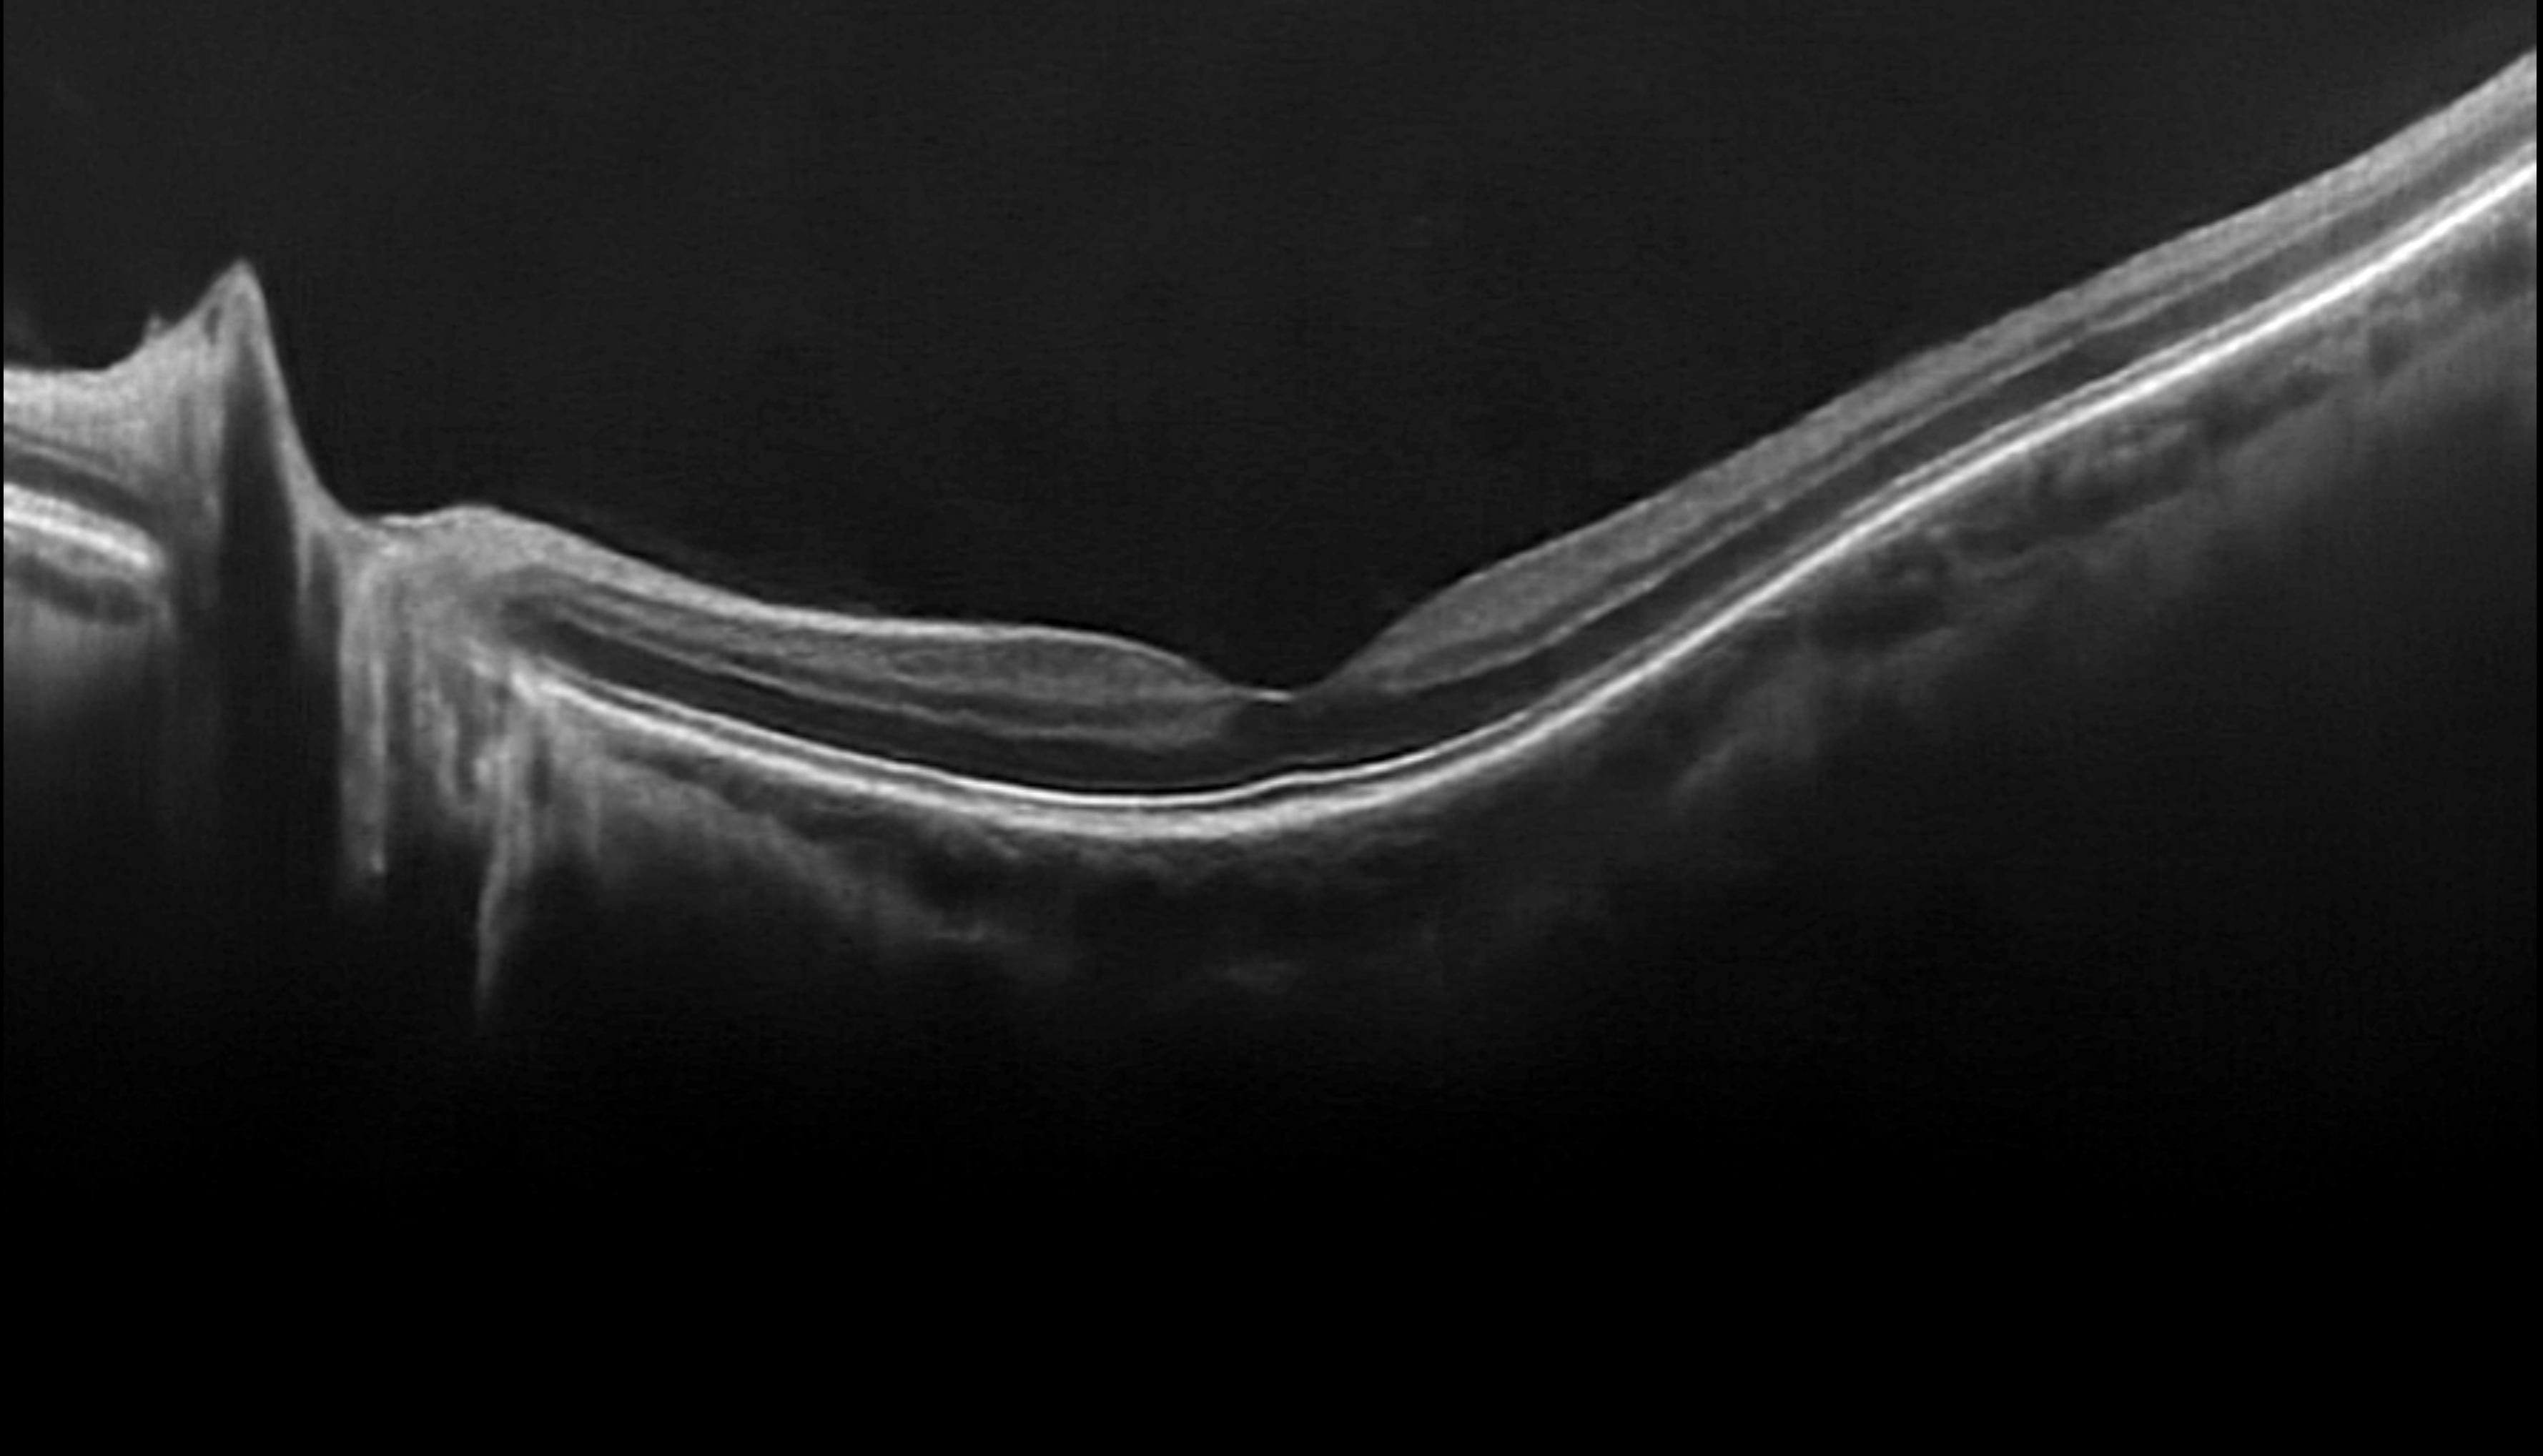

Optical Coherence Technology (OCT) uses light waves to take cross-section pictures of your retina. With OCT, you can see each of the retina’s distinctive layers. This allows you to map and measure their thickness which will assist in diagnosis and provide treatment guidance for retinal diseases such as, but not limited to; glaucoma, diabetic eye disease, and AMD. These measurements help with diagnosis.